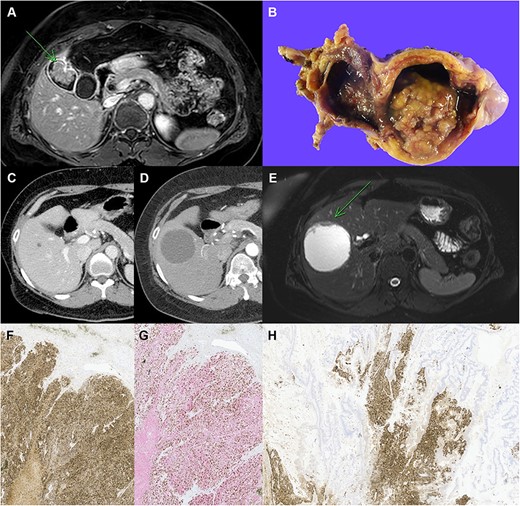

For further information, magnetic resonance imaging (MRI) and positron emission tomography (PET)-CT scan were performed, and MRI also revealed a 3.5 cm sized enhancing villous mass in GB body, suggesting GB cancer (Fig. 1A). Two tiny low attenuating lesions in segment V and VI of the liver were likely to be cysts, suggesting non-malignancy. PET-CT revealed increased fludeoxyglucose (FDG) uptake in the GB body mass, which was suspected to be malignant, and discernible FDG uptake was not found in the liver.

Clinicopathological images of the patient. (A) Preoperative MRI showing GB cancer, (B) gross specimen of GB with papillary tumor, (C, D) follow-up imaging showing the increased size of cystic lesion in the liver, (E) MRI showing cystic mass in segment V with enhancing mural nodule and wall thickening, (F) immunohistochemical staining with chromogranin A, (G) synaptophysin (red) and Ki-67 (brown) double staining in neuroendocrine carcinoma of the liver, (H) chromogranin A staining in the GB tumor, which reveals neuroendocrine component (original magnification: ×100).

Based on her imaging findings, laparoscopic radical cholecystectomy was planned under the impression of GB cancer. The specimen showed a 4-cm-sized papillary mass and pathologic examination confirmed well-differentiated adenocarcinoma without lymph node metastasis (T2aN0M0, Stage IIA) (Fig. 1B).

After the surgery, the patient received adjuvant gemcitabine chemotherapy and was followed-up in outpatient settings. A series of follow-up CT showed a growing cyst in the S5 liver segment (Fig. 1C and D). Therefore, MRI was performed for differential diagnosis, which showed a growing 7-cm-sized cystic mass with enhanced mural nodule and wall thickening (Fig. 1E). Right lobectomy of the liver was planned for the possibility of malignancy.

After the surgery, pathological findings of the specimen revealed neuroendocrine carcinoma (NEC) sized 8 cm. The tumor contained extensive necrosis, with mitotic index 2/10 HPF and focal glandular differentiation of < 5% (Fig. 1F). The Ki-67 index was about 70%, and the subtype of the NEC was large cell NEC (LCNEC) (Fig. 1G).

The most likely diagnosis was metastatic tumor of the liver, and thus thorough diagnostic work-up for primary tumor site was performed. Ga-68 DOTATOC PET-CT was performed; however, the site of primary origin could not be located. In extension of finding the origin of the NET, a review of the previously resected GB specimen was conducted. The review found a neuroendocrine component in the specimen, which was previously unseen. The neuroendocrine component was positive for chromogranin A, synaptophysin and CD56 in immunohistochemical staining, and the specimen was rediagnosed as MiNEN consisting of adenocarcinoma and LCNEC (Fig. 1H).